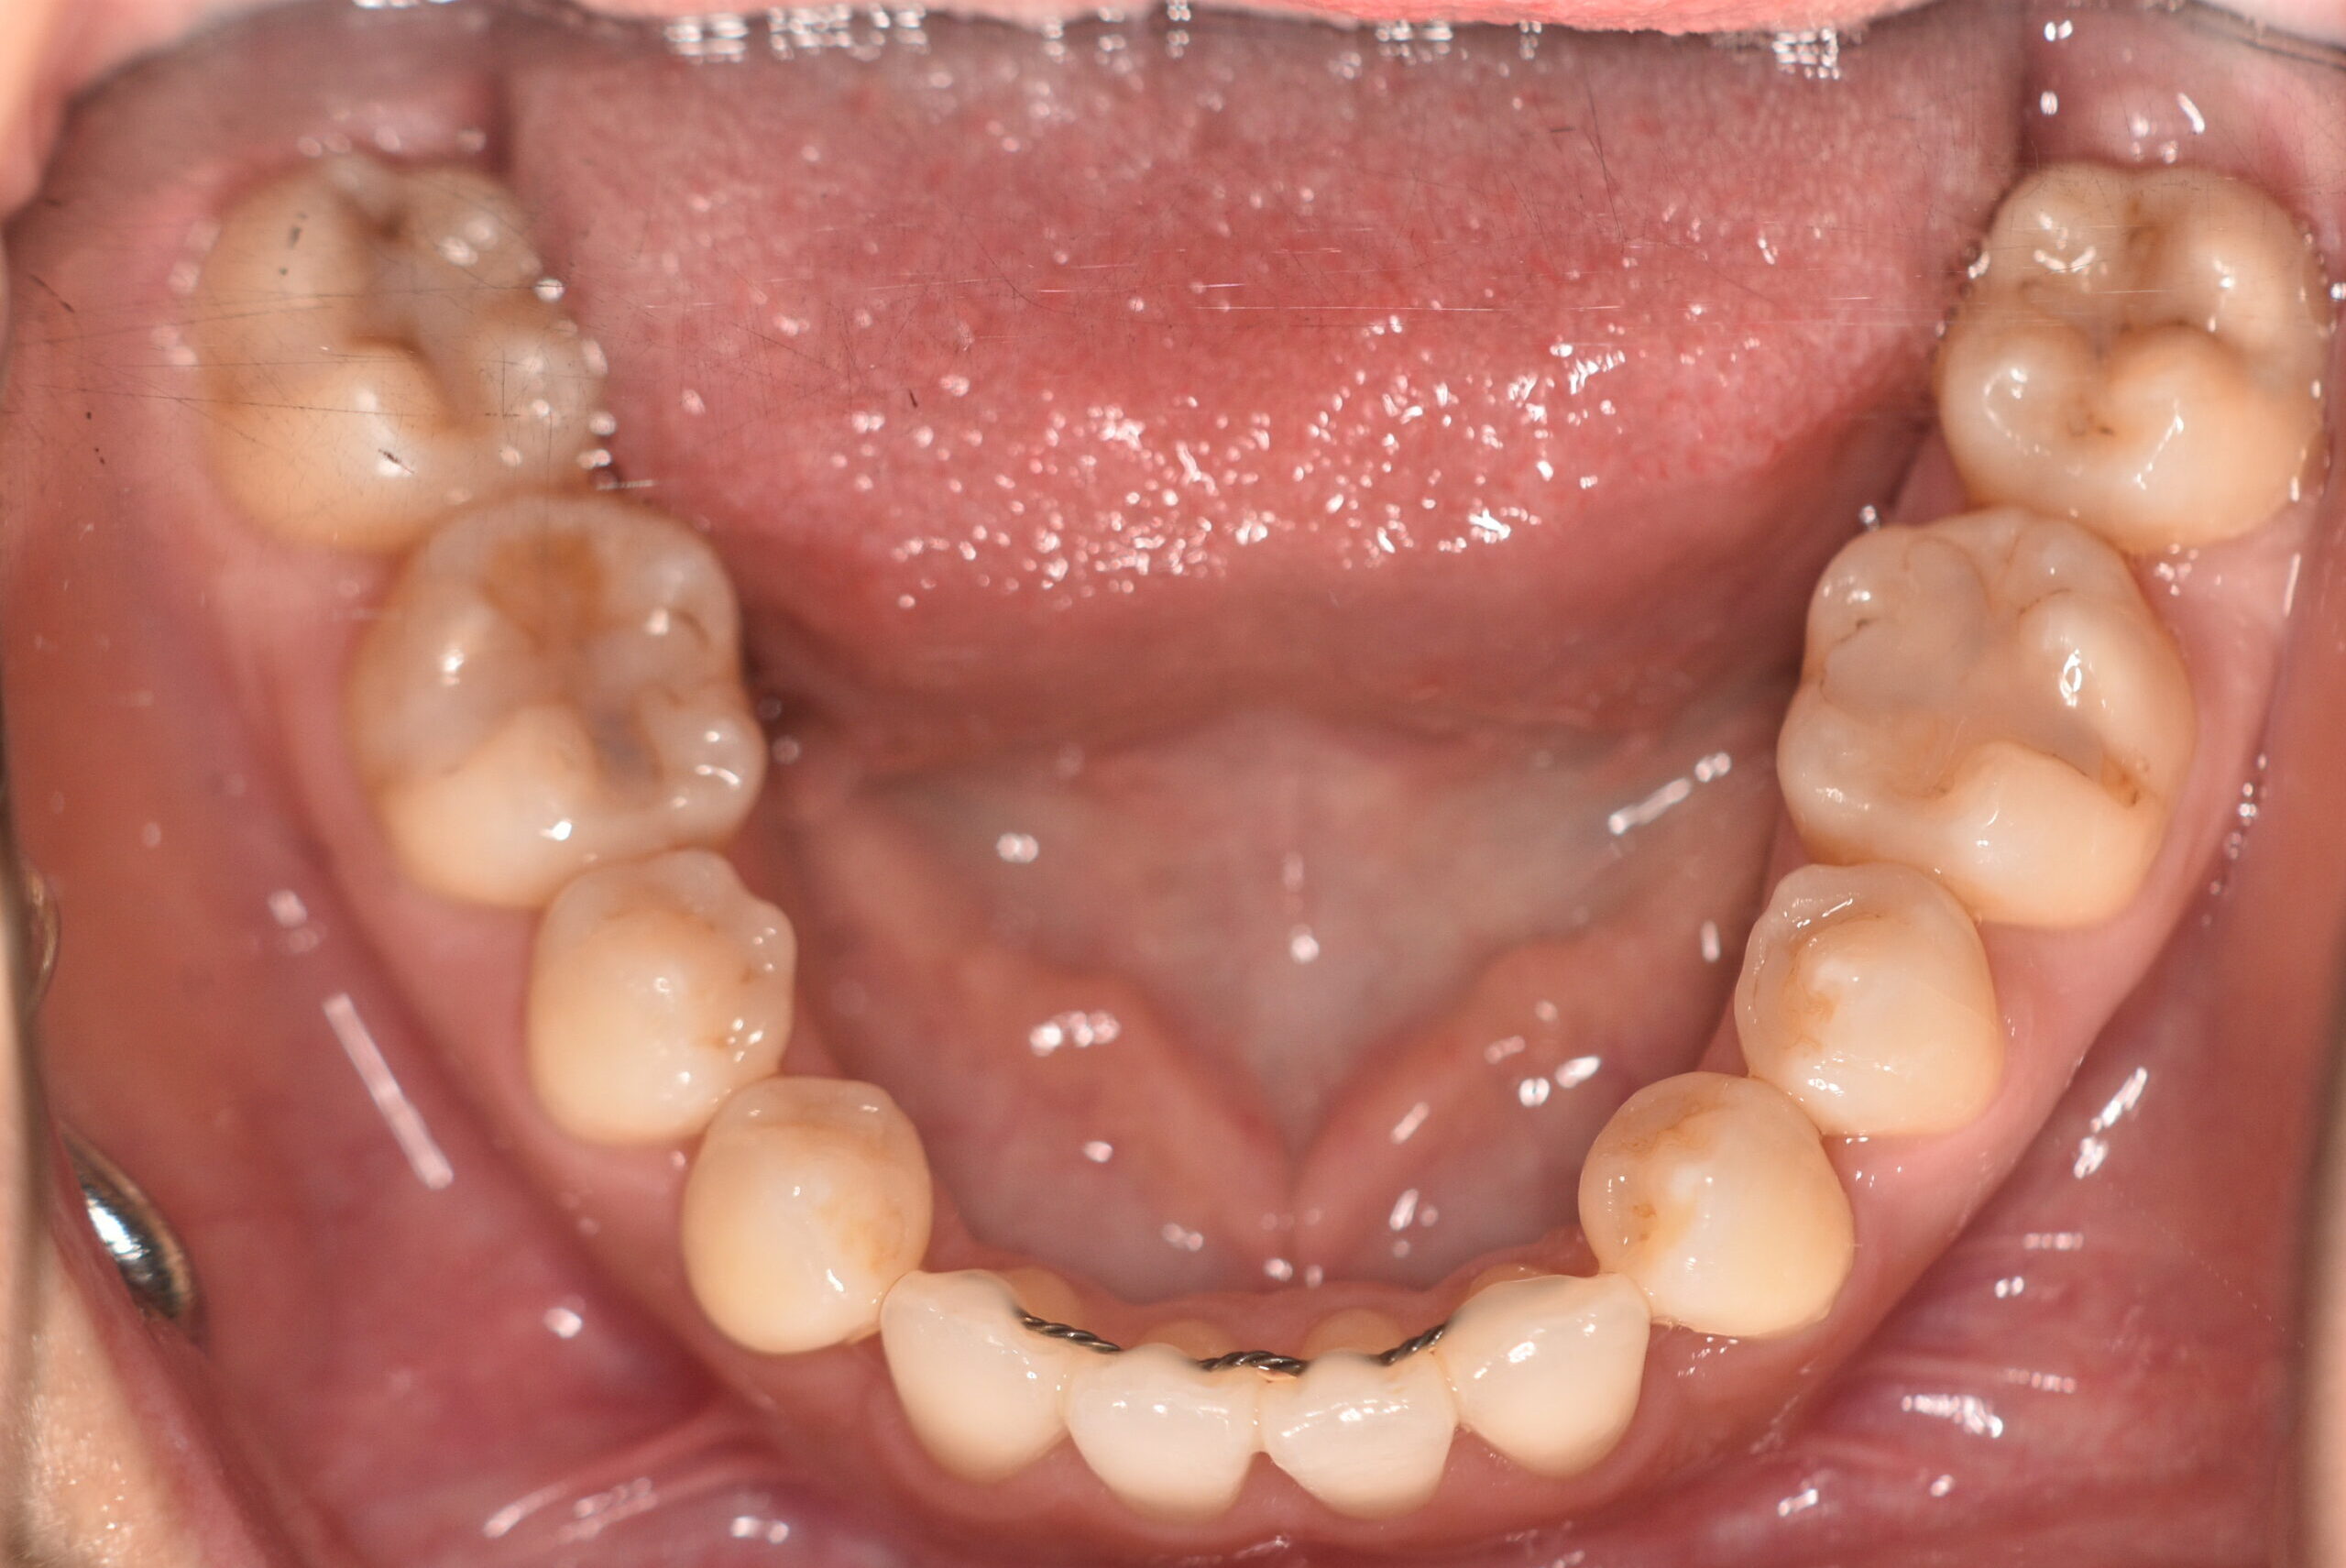

動的治療終了時

症例 症例 症例 症例 症例